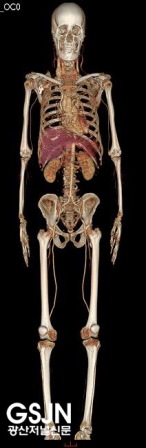

º»¿ø¿¡¼­ µµÀÔÇÑ Volume CTÀÇ Å« Ư¡Àº ÀÎüÀÇ ¸ðµç ºÎÀ§¸¦ °¡Àå º¸±â ÁÁÀº ¿µ»óÀ¸·Î °Ë»çÇÒ ¼ö ÀÖ´Ù´Â °Í°ú °¡Àå ¿ì¼öÇÑ ¼º´É°ú ÃÖ°íÀÇ È­ÁúÀ» ÀÚ¶ûÇÏ´Â °Ë»ç±â±âÀÔ´Ï´Ù.

¶ÇÇÑ °Ë»ç¸¦ ¹ÞÀ¸½Ã´Â ȯÀÚ¿¡°Ô ¹æ»ç¼±ÇÇÆø¼±·®À» ÃÖ¼Ò·Î ÇÒ ¼ö ÀÖ°í ¸ðµç ºÎÀ§ÀÇ ¿µ»óÀ» 0.35mm±îÁö ±¸º°ÇÒ ¼ö ÀÖ´Â ¿µ»óÈ­ÁúÀ» °¡Áö°í ÀÖÀ¸¸ç Àü½ÅÀ» °Ë»çÇϴµ¥ ÀÖ¾î ȯÀÚÀÇ °íÅëÀ» ¼ö¹ÝÇÏÁö ¾ÊÀ¸¸é¼­ ±âÁ¸ÀÇ Àåºñº¸´Ù ÈξÀ ºü¸£°í Á¤È®ÇÏ°Ô °Ë»ç¸¦ ¹ÞÀ¸½Ç ¼ö ÀÖ½À´Ï´Ù. ÀÌ·¯ÇÑ Àåºñ¸¦ µµÀÔÇÔÀ¸·Î¼­ º»¿øÀ» ÀÌ¿ëÇϽô °í°´¿©·¯ºÐÀÇ Áúº´À» »çÀü¿¡ ¿¹¹æÇϰí Á¶±â¿¡ Áø´ÜÇÒ ¼ö ÀÖÀ¸¸ç º¸´Ù Á¤È®ÇÏ°Ô Áø´ÜÇÒ ¼ö ÀÖÀ¸¸ç ¹æ»ç¼± ÇÇÆøÀÌ ÀûÀº ÃÖ÷´Ü °Ë»ç°¡ °¡´ÉÇÏ°Ô µÇ¾ú½À´Ï´Ù.